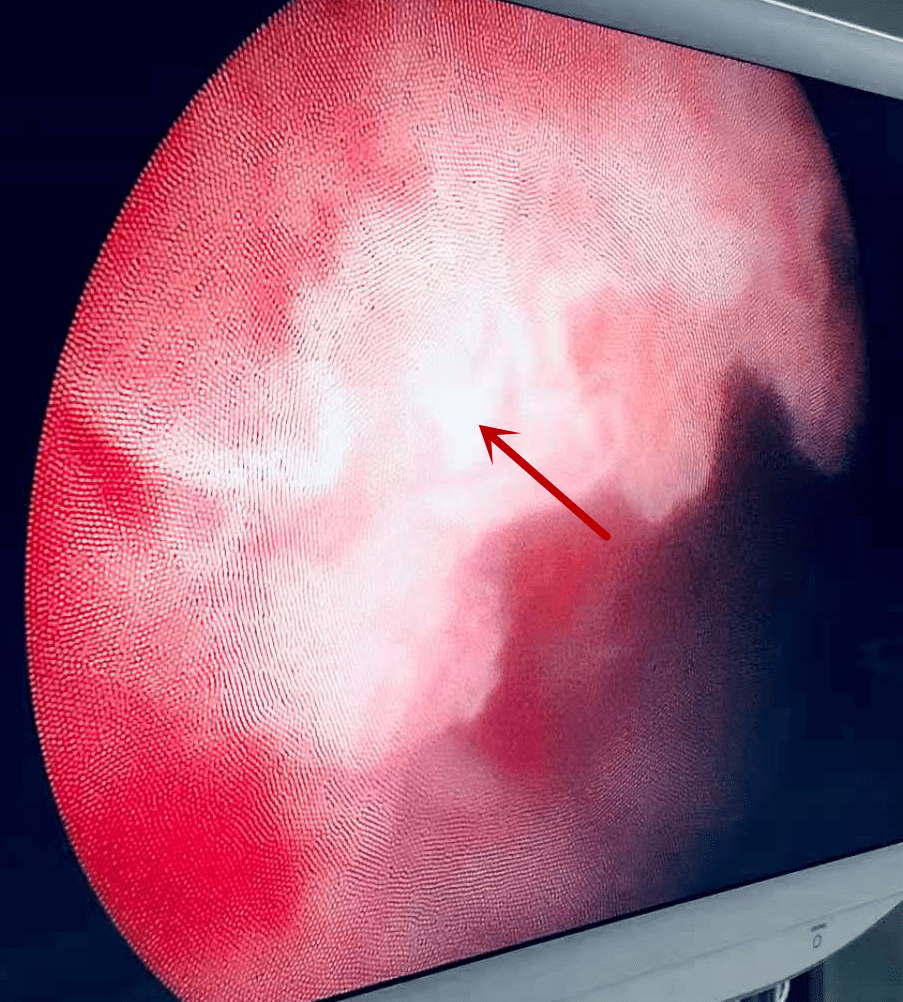

摩西钬激光前列腺剜除术展示 高效钬激光剜除一气呵成 止血效果好,不

激光前列腺剜除术优点:切除彻底,出血少,特别是大前列腺;但是需要专业

成人和小儿上尿路结石碎石术,超微经皮肾镜取石术,钬激光前列腺剜除术